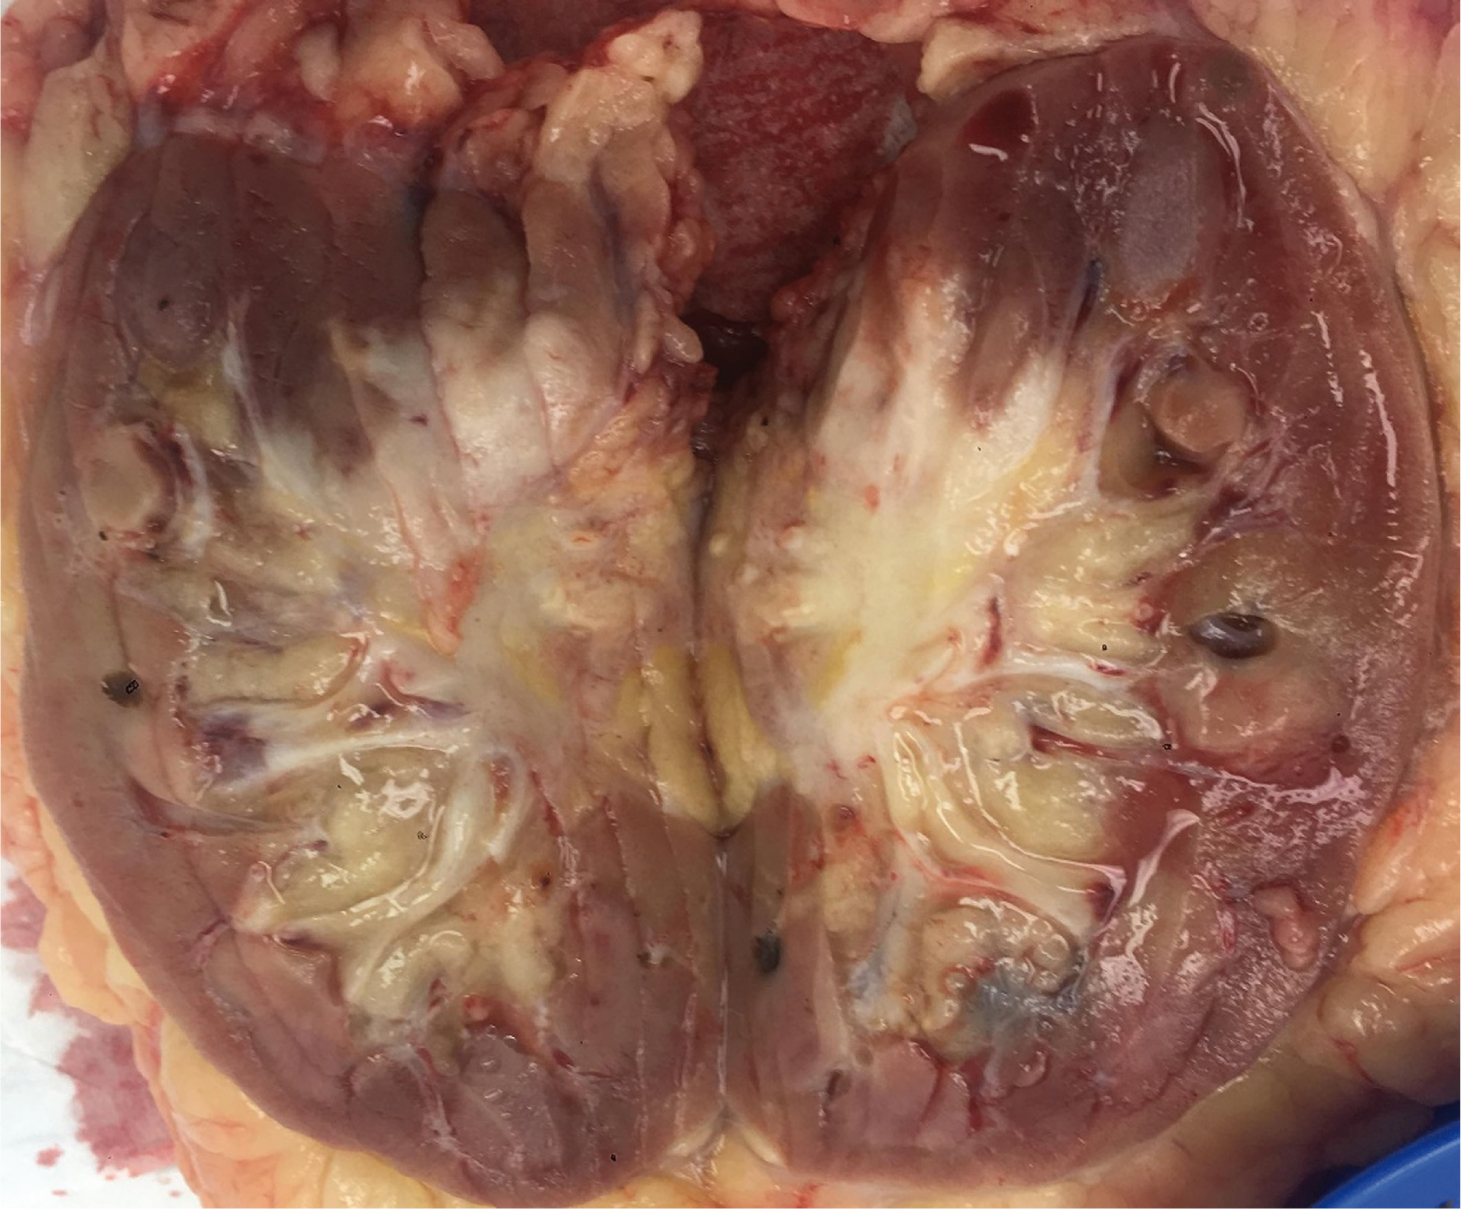

Macroscopic features showed a 45 mm cream-coloured tumour in the mid- to upper pole with no haemorrhage or necrosis (Figure 2). The tumour showed invasion through the IVC wall, extending into the psoas muscle. Histopathology demonstrated a moderately differentiated SCC with associated fibrosis (Figure 3). The tumour also showed extensive lymphovascular invasion and peri-neural invasion involving the vascular margin. Two of the five resected hilar lymph nodes demonstrated involvement, whereas the one resected pre-aortic lymph node did not demonstrate involvement. The patient was referred to a radiation oncologist to discuss the possibility of adjuvant radiotherapy.

Fig 2

Figure 2. Pathological specimen of right kidney post-nephrectomy demonstrating a dense hilar mass.